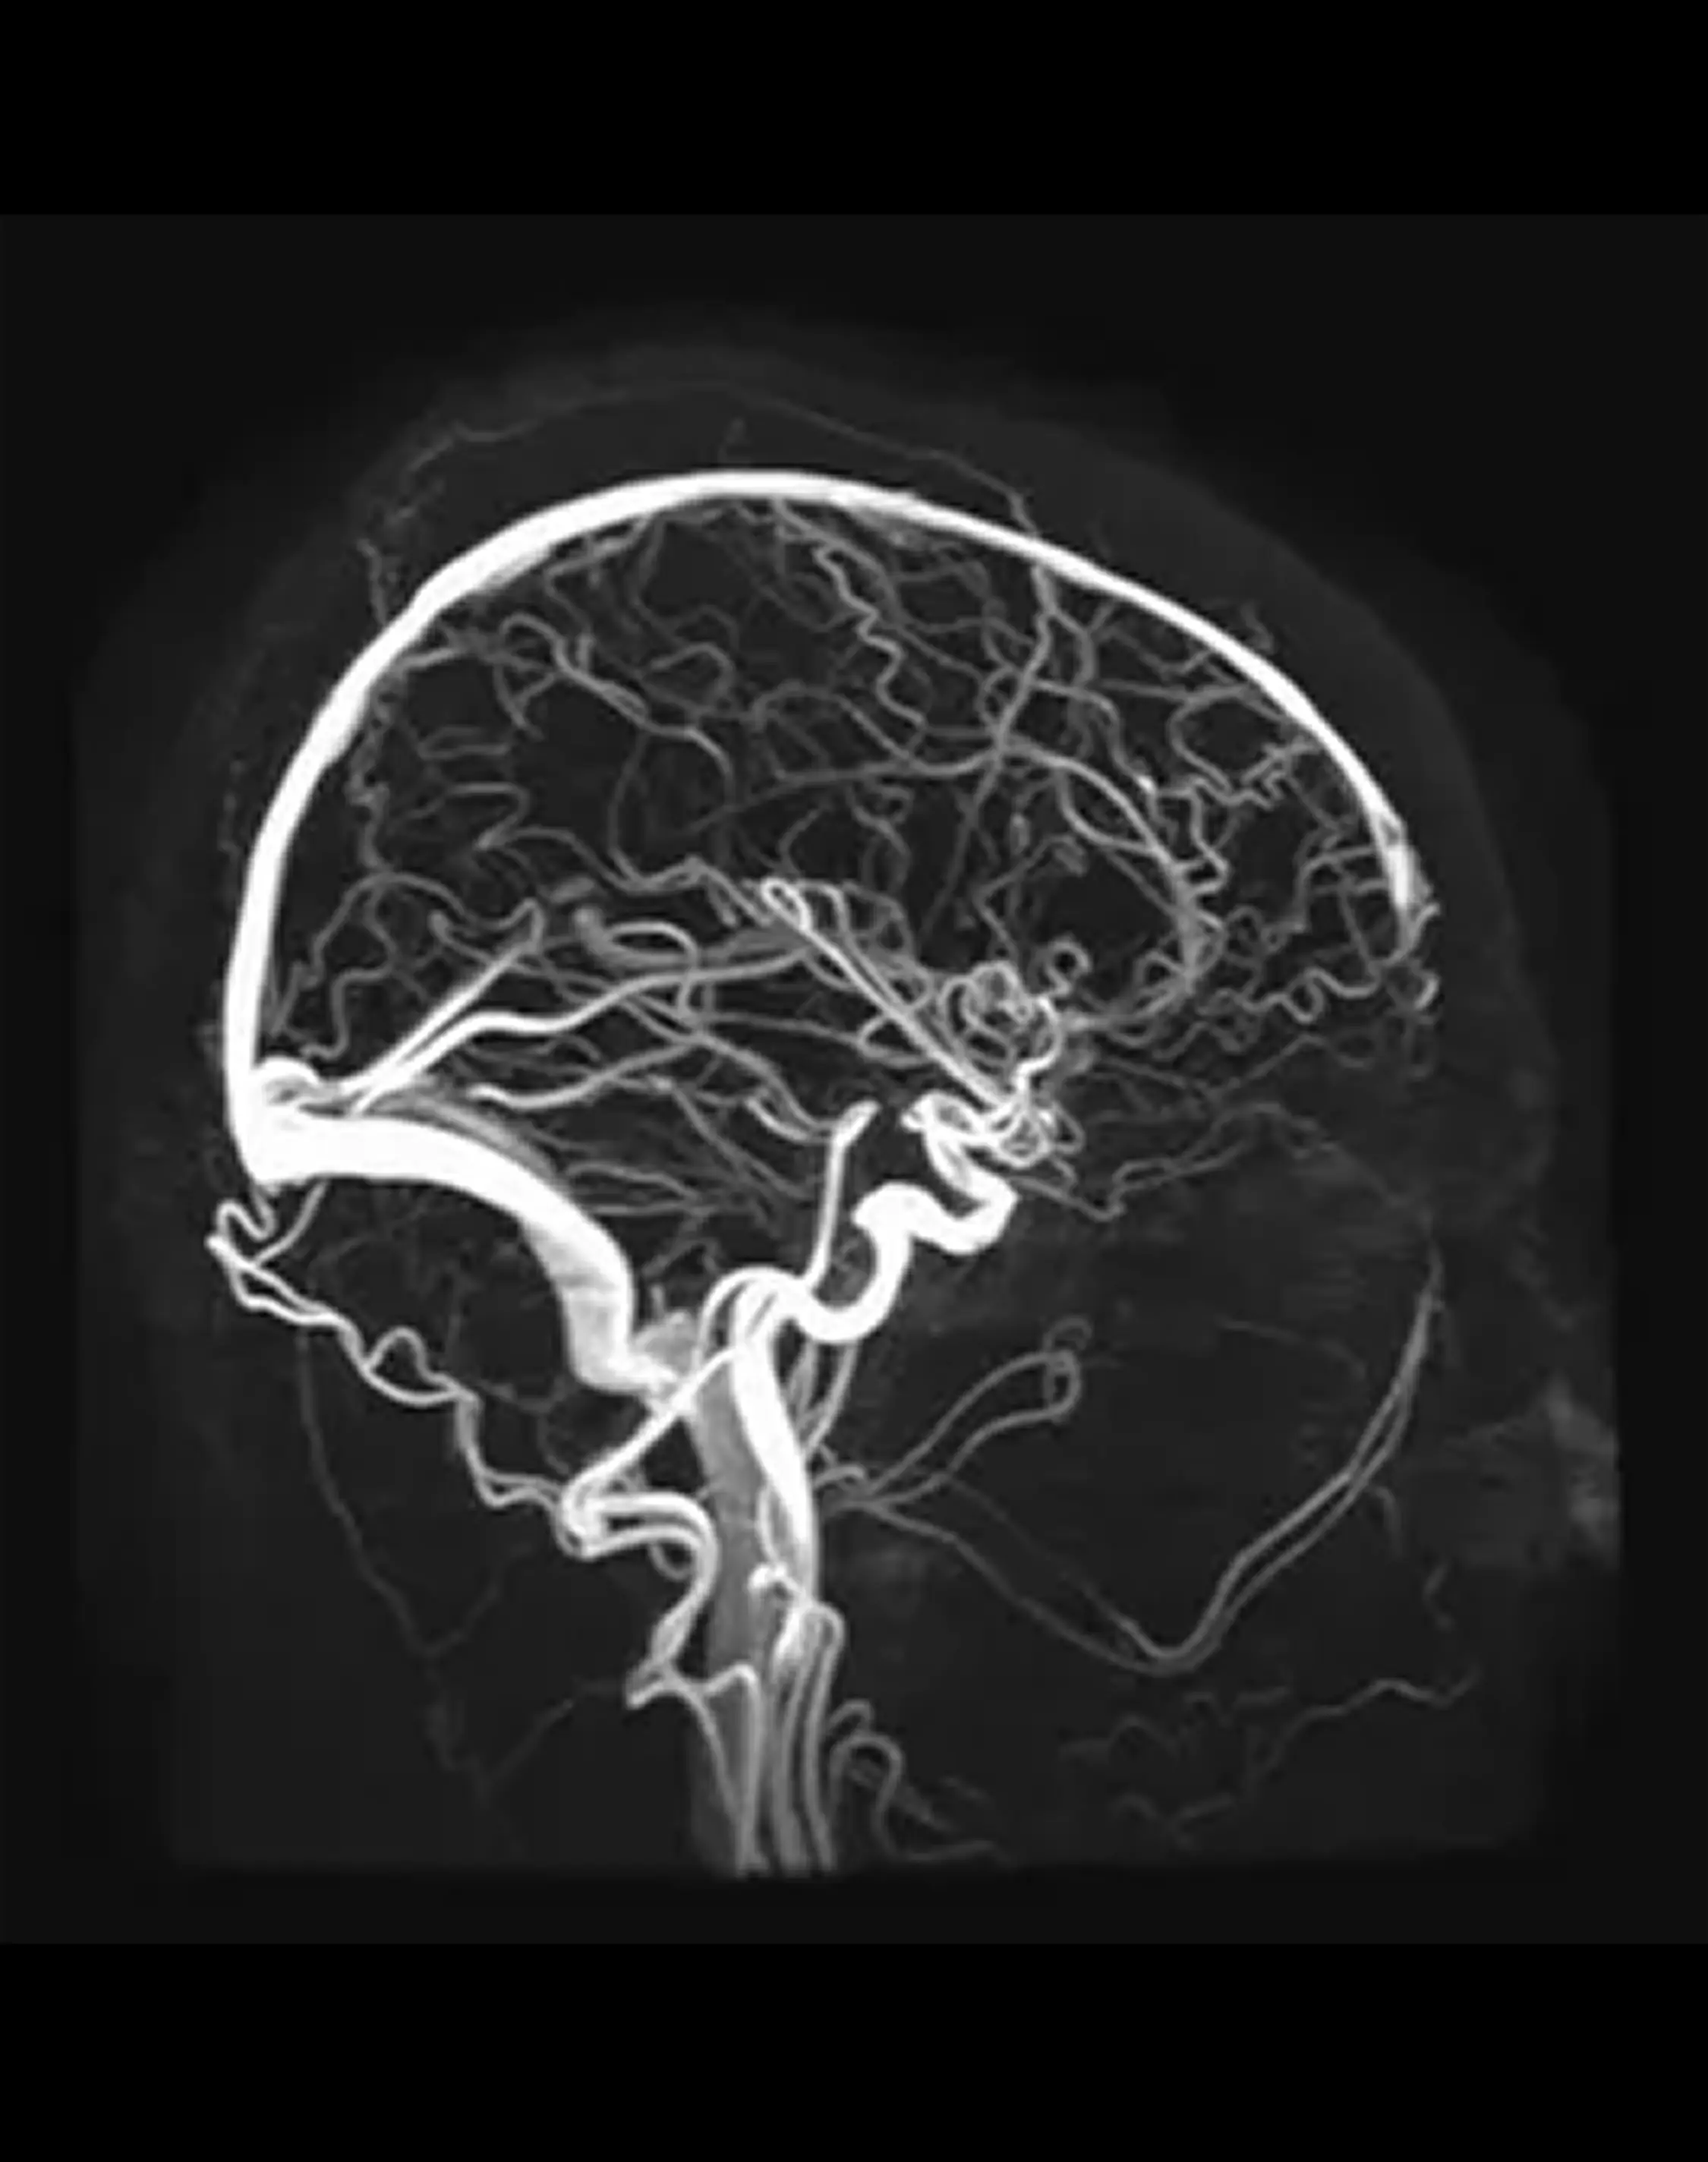

МРТ вен головного мозга (венография, венозные синусы)

Позволяет визуализировать венозный отток по синусам и венам.